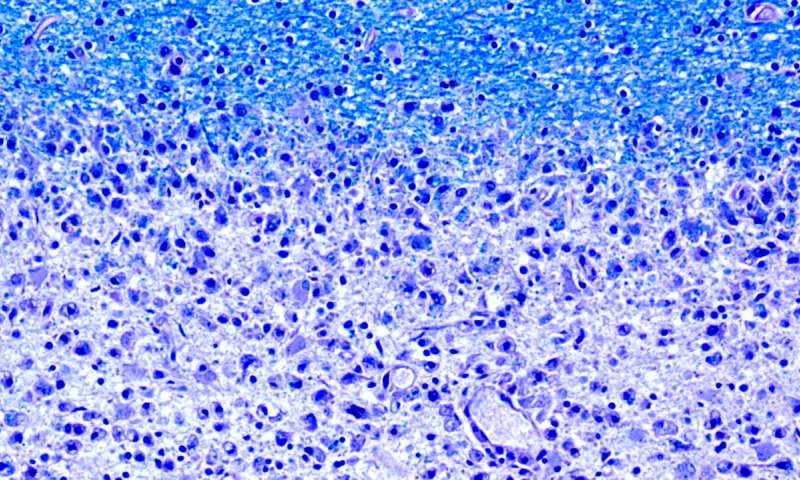

Immagine: riduzione delle guaine mieliniche: le aree danneggiate (nella parte inferiore dell’immagine) del cervello dei pazienti affetti da sclerosi multipla mancano di mielina (nella parte superiore, in blu). (Immagine: Dr. med. Imke Metz, Università di Göttingen, Germania) Credito: Dr. med. Imke Metz, Università di Göttingen, Germania.

La sclerosi multipla si sviluppa quando il sistema immunitario inizia ad attaccare erroneamente la mielina, un isolante ricco di lipidi che copre le terminazioni nervose. Le persone con SM generalmente sviluppano formicolio e intorpidimento e, nel tempo, una miriade di altri sintomi. Non esiste attualmente alcuna cura e il trattamento è limitato ai tentativi di migliorare la funzionalità.